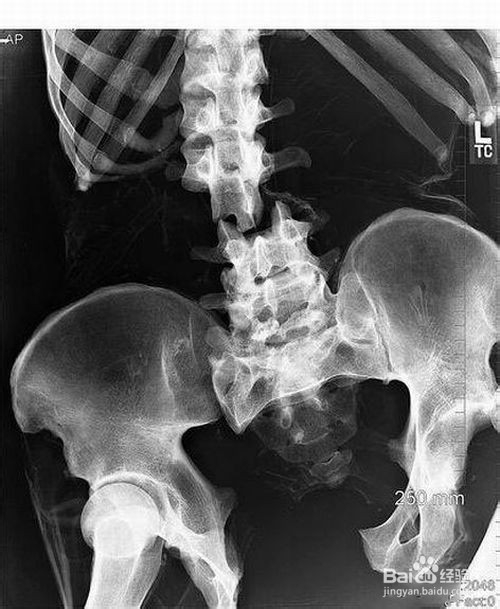

3、3.脊柱、骨盆部骨折:脊柱骨折 120日;骨盆稳定型骨折 90日~120日;骨盆不稳定型骨折 120日~180日